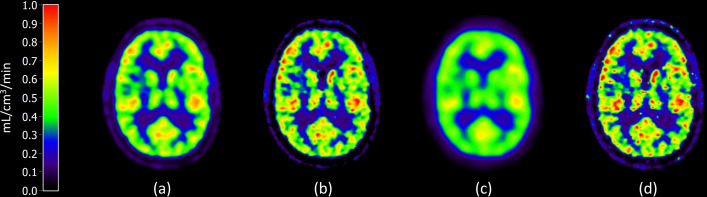

Results: The mean whole brain CBF was 0.48 mL/cm3/min and showed little dependence on the image reconstruction method. Grey matter CBF varied between 0.52 and 0.57 mL/cm3/min, and central white matter CBF between 0.20 and 0.28 mL/cm3/min. Regional CBF showed great dependence on effective spatial resolution with a negative correlation between grey matter CBF and resolution (r = -0.96) and a positive correlation between central white matter and resolution (r = 0.93).

Conclusion: This study concludes that grey matter and central white matter CBF, but not whole brain CBF measured with quantitative 15O-water PET is reconstruction method dependent, mainly due to varying spatial resolution with consequent partial volume effects. Variations in published CBF values cannot be explained solely by reconstruction methods or spatial resolution.